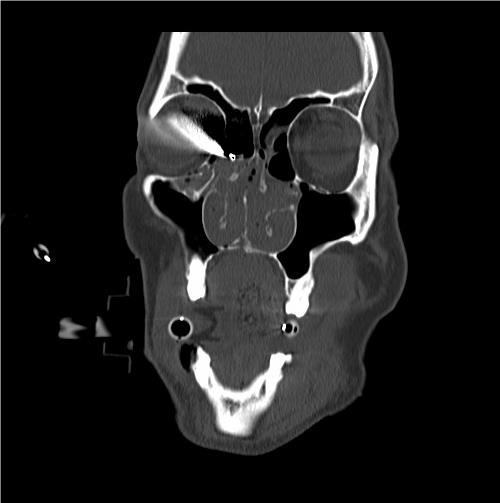

INTRAORBITAL FOREIGN BODY

EXAM

Intraorbital foreign body visible on examination or identified on diagnostic imaging such as X-ray or CT.

Figure 23. Intraorbital foreign body. Bullet in right orbit. Photo credit: LTC Won Kim.